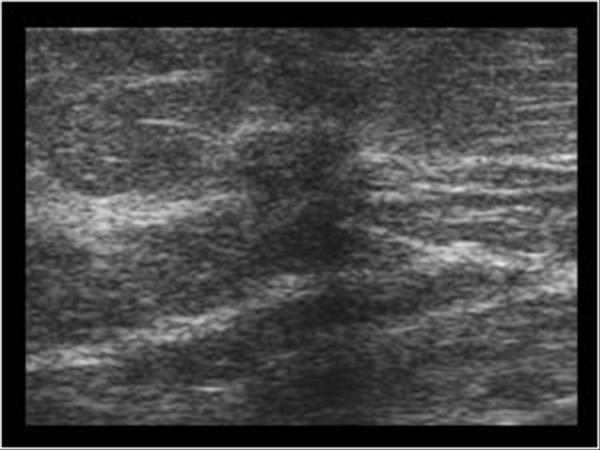

What are Malignant conditions?

cancerous disorders that can affect the breast

What is the Sonographic Appearance of malignant breast lesions?

Taller than wide

Angular, ill-defined, microlobulations

Thick borders

Echogenic halo

Almost anechoic, heterogenous

Shadowing

Color Doppler - more peripheral and internal flow

Invade tissue planes

What is Invasive Ductal Carcinoma (IDC)?

malignant breast condition

80% of Breast cancer. Begin in the duct and invade the fatty tissue. Potential for metastases

What is the Sonographic Appearance of Invasive Ductal Carcinoma (IDC)?

Calcifications

Ductal enlargements

Invasion of the breast parenchyma